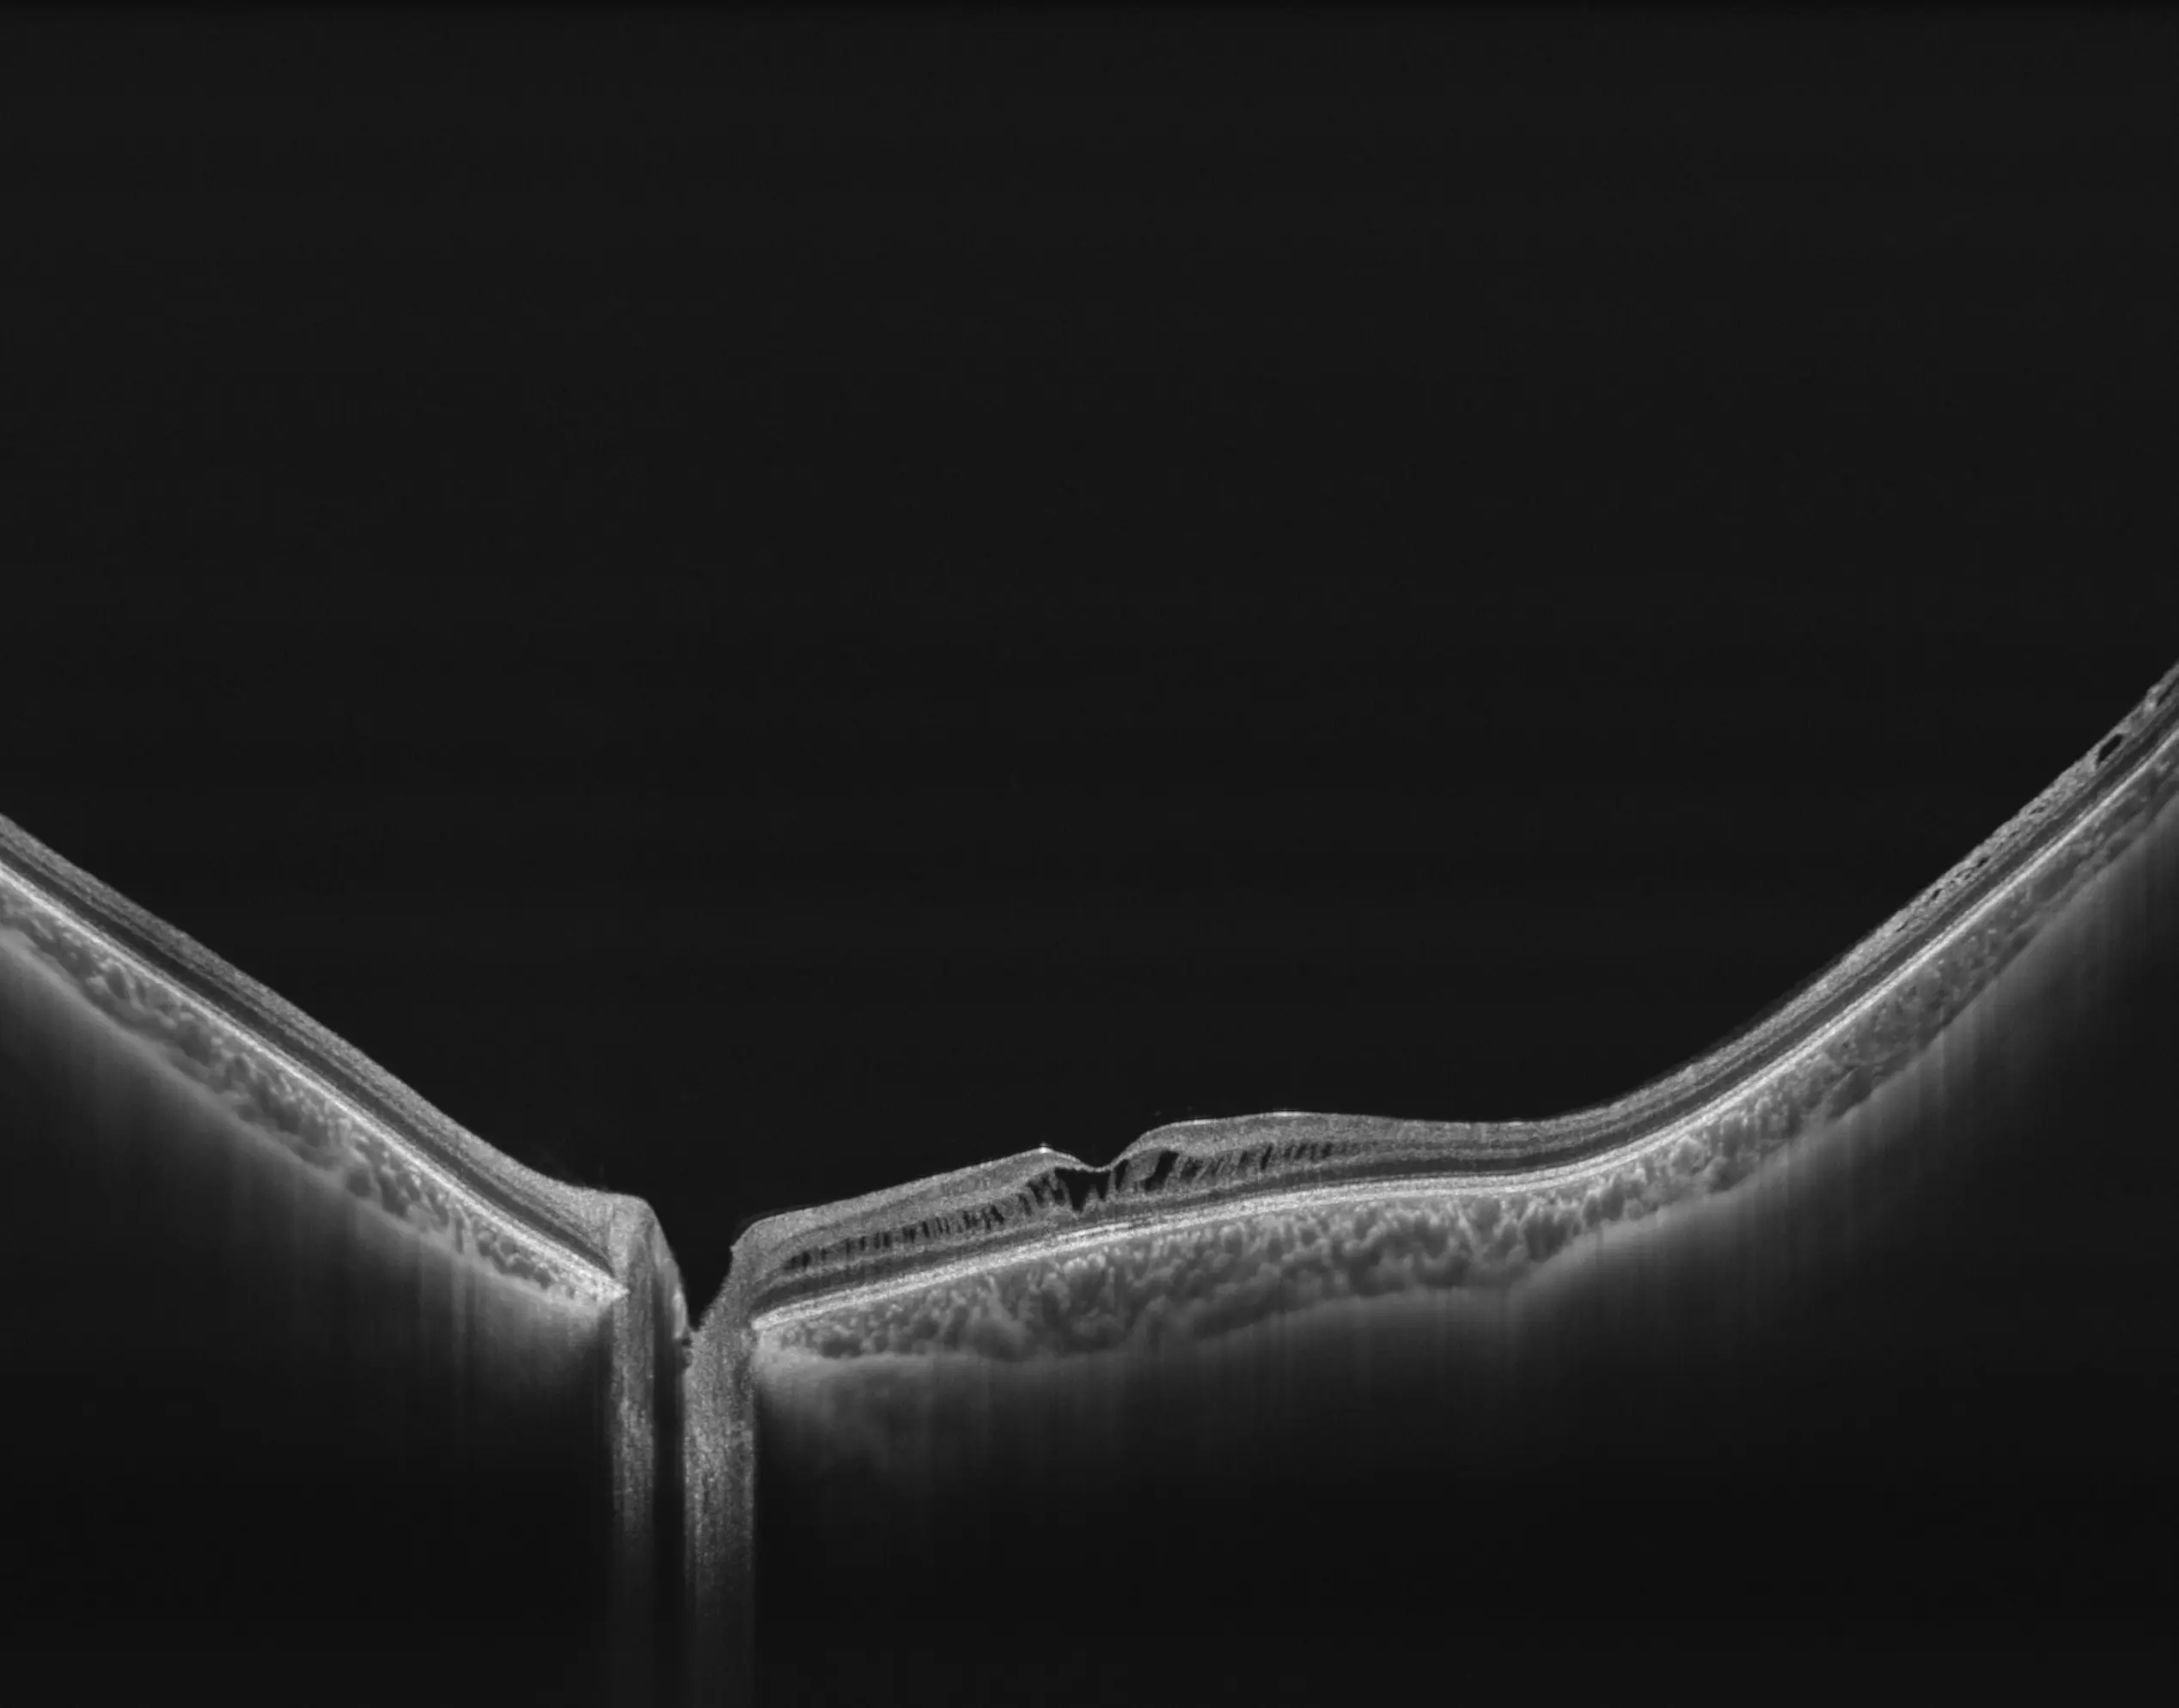

Oba systemy osiągają rozdzielczość osiową ≤ 6 µm oraz ultra-wysoką gęstość wokseli (do 10 mld w BMizar), Pozwalają uwidocznić najdrobniejsze struktury siatkówki, naczyniówki i segmentu przedniego oka.

NIEZRÓWNANA JAKOŚĆ OBRAZOWANIA

Pełna diagnostyka

w jednym ujęciu